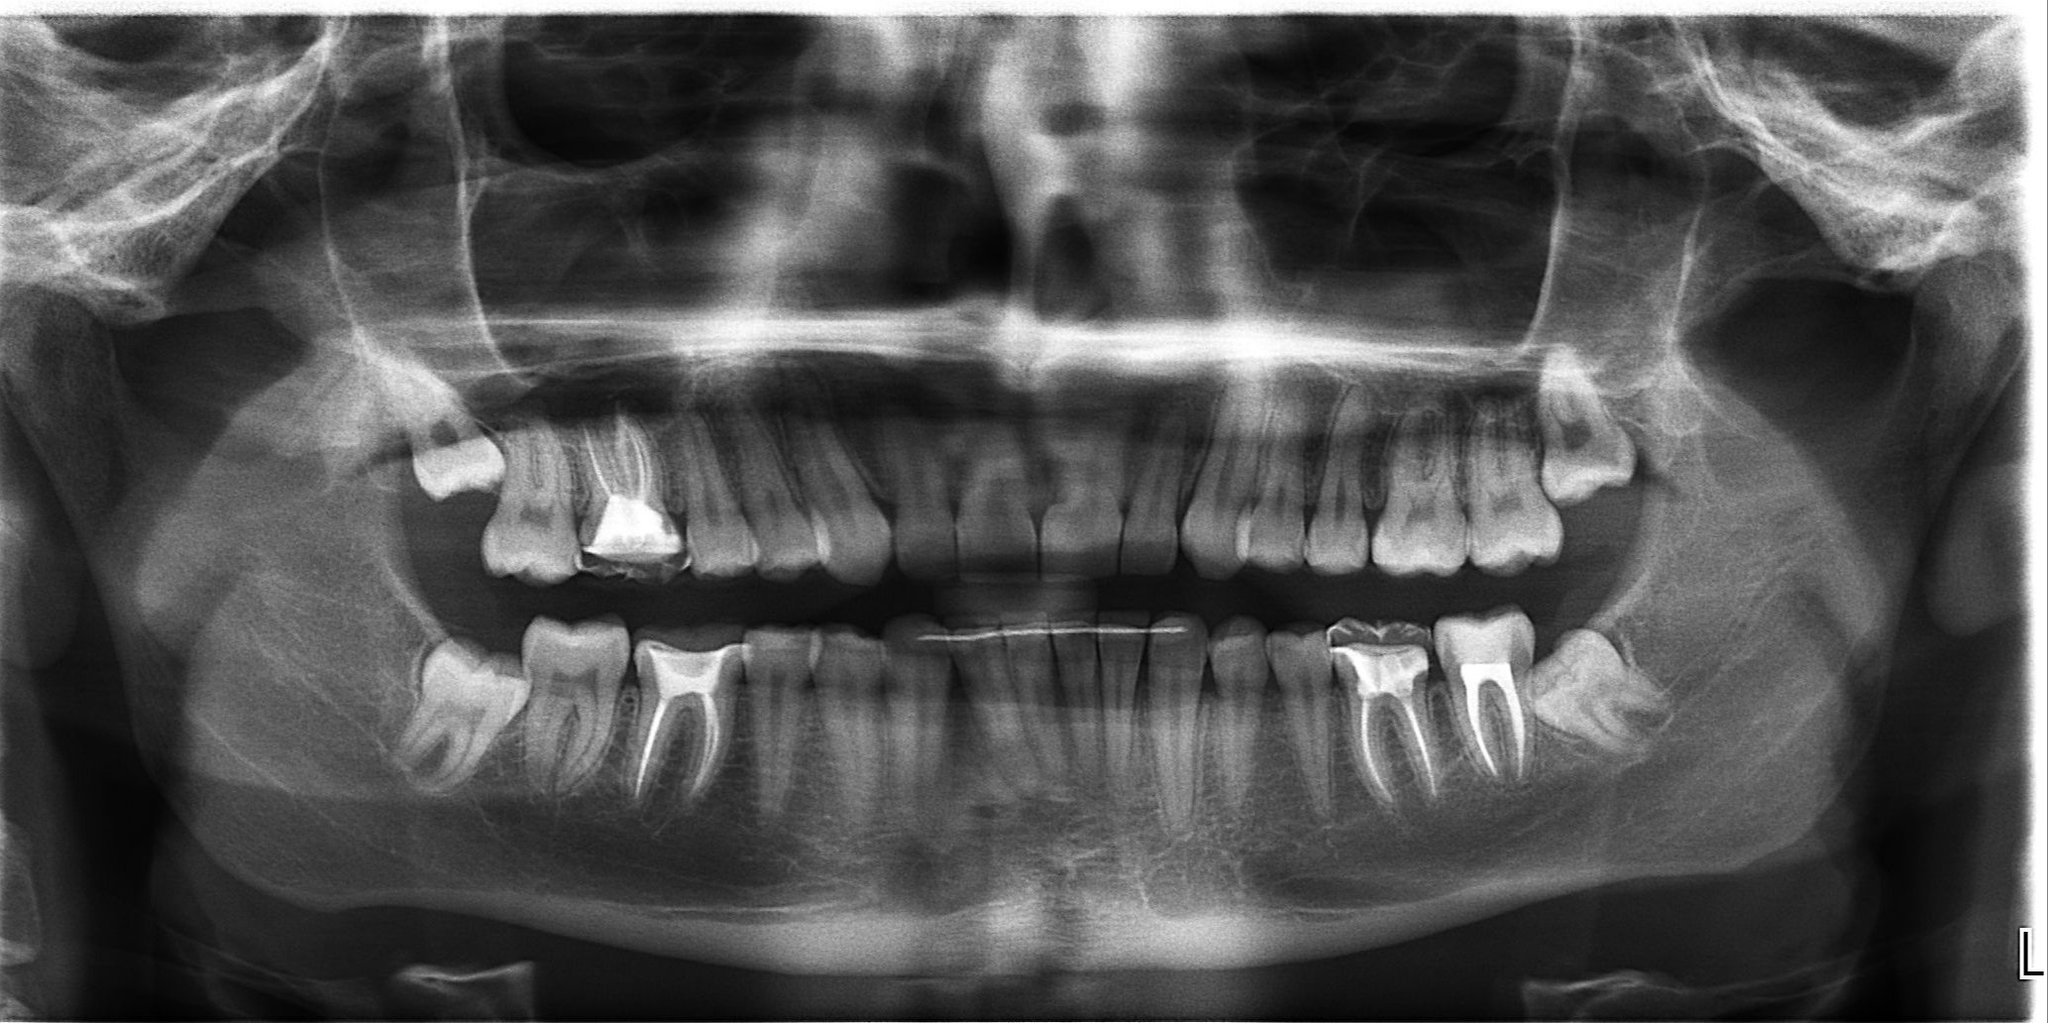

Стоматологические Исследования: Рентген Инвагинации Зубов